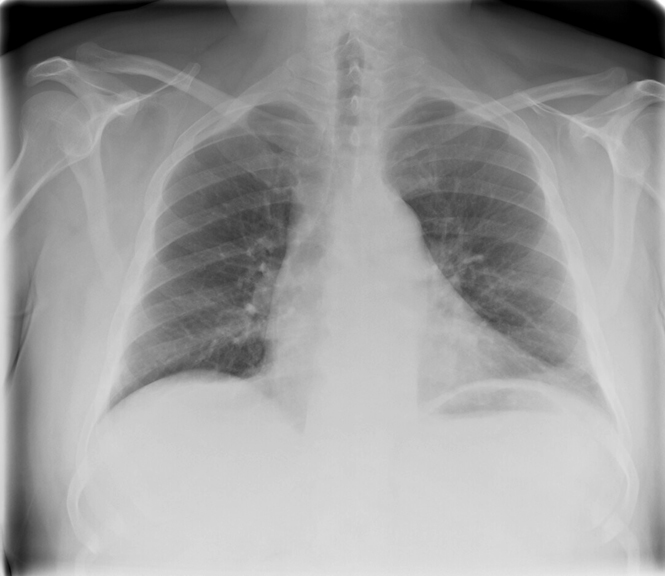

Fat Pad